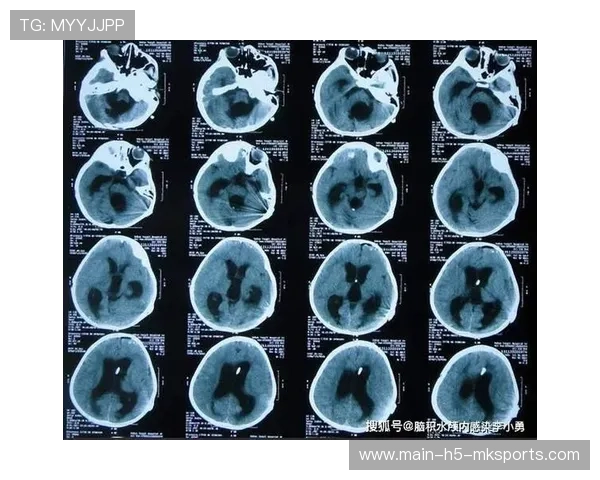

运动干扰:CT扫描是一种静态成像技术,需要患者在扫描过程中保持完全静止。如果患者在扫描过程中不能控制呼吸或不能保持静止,会导致影像模糊,影响诊断效果。体型影响:体型过大的患者在CT扫描过程中可能会受到设备的限制,导致图像质量下降。尤其是在重建算法和剂量控制方面,体型较大的患者可能会面临更多的技术挑战。

病理特点:某些病理特点,如肿瘤的微小性、病变的隐匿性等,可能会使CT检查难以捕捉到细节,导致检查结果不准确。

设备问题:CT设备本身的性能和维护情况直接影响检查结果。设备老化、机械故障或软件错误等问题都可能导致CT失败。操作失误:CT扫描是一项高度依赖技术操作的检查,如果操作不当,例如扫描范围设置错误、剂量设置不当等,都会影响诊断结果。图像处理问题:CT图像的重建算法和后处理技术的选择,直接影响最终的影像质量。